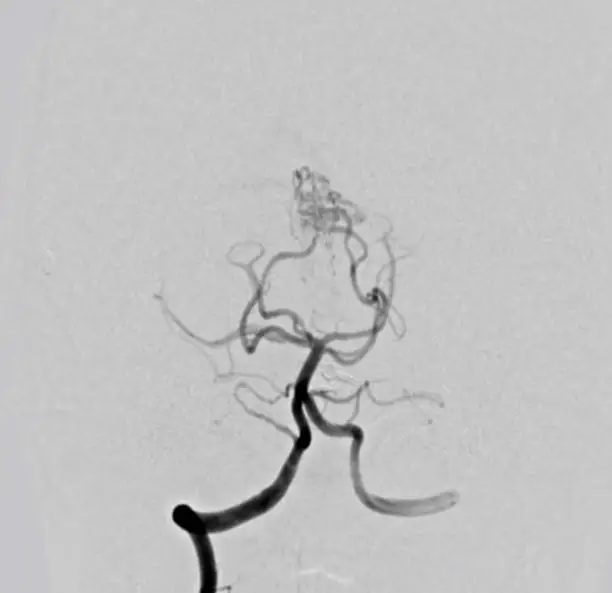

심혈관 조영술로 알 수 있는 질병은?

심혈관 조영술은 혈관 내로 조영제를 주입한 후 X선을 이용해 혈관을 시각화하는 검사입니다. 이 검사를 통해 다양한 심혈관 질환을 진단할 수 있으며, 특히 심장과 주요 혈관의 이상을 탐지하는 데 매우 유용합니다. 심혈관 질환은 조기에 발견하고 관리해야만 더 심각한 합병증을 예방할 수 있기 때문에, 심혈관 조영술은 많은 환자들에게 중요한 검사로 인식되고 있습니다. 심혈관 조영술로 알 수 있는 질병은 여러 가지가 있으며, 이를 통해 심장 건강을 더욱 철저히 관리할 수 있습니다.

심혈관 조영술로 가장 흔히 발견되는 질병 중 하나는 관상동맥 질환입니다. 이 질환은 심장을 둘러싼 관상동맥이 좁아지거나 막히는 상태를 의미합니다. 관상동맥은 심장에 산소와 영양분을 공급하는 중요한 혈관이므로, 이 혈관이 좁아지면 심장 기능이 저하되고 심장 마비 등의 심각한 결과를 초래할 수 있습니다. 조영술은 이러한 동맥의 막힘 정도를 시각적으로 확인할 수 있어 치료 계획을 세우는 데 결정적인 역할을 합니다. 조영술을 통해 관상동맥이 좁아진 부위를 정확히 파악할 수 있으며, 이후 적절한 시술이나 약물 치료가 이루어지게 됩니다.

관상동맥 질환은 주로 동맥경화로 인해 발생하며, 이는 지방 성분이나 콜레스테롤이 혈관 벽에 쌓여 혈액의 흐름을 방해하는 현상입니다. 조영술을 통해 동맥경화의 진행 상태를 정확히 알 수 있으며, 이를 바탕으로 혈관 확장술이나 스텐트 삽입 등의 시술이 결정됩니다. 심혈관 조영술은 비단 질병 진단뿐만 아니라, 향후 치료 방향을 결정하는 데도 큰 도움이 됩니다.

심혈관 조영술을 통해 알 수 있는 또 다른 질병은 심근경색입니다. 심근경색은 흔히 심장마비라고 불리며, 심장 근육에 혈액 공급이 차단되어 심장 조직이 손상되는 질환입니다. 이는 관상동맥이 갑작스럽게 막히면서 발생하는데, 조영술은 이러한 막힘을 즉각적으로 확인할 수 있어 응급 치료를 가능하게 합니다. 심근경색이 의심되는 상황에서 신속한 조영술은 환자의 생명을 구하는 데 중요한 역할을 합니다.

심근경색이 발생하면 즉각적인 치료가 필요하며, 조영술을 통해 혈관의 막힘을 정확히 확인한 후에는 혈전 용해제나 스텐트 시술 같은 치료법을 빠르게 시행할 수 있습니다. 조영술로 혈관 상태를 명확히 파악함으로써 더 이상 손상이 일어나지 않도록 하는 것이 치료의 핵심입니다. 심근경색은 조기에 발견하고 치료하지 않으면 심장 기능이 급격히 저하되어 사망에 이를 수 있는 심각한 질병입니다.

대동맥 질환은 심혈관 조영술을 통해 확인할 수 있는 또 다른 중요한 질환입니다. 대동맥은 심장에서 몸 전체로 혈액을 공급하는 주요 동맥으로, 대동맥의 기능 장애는 매우 위험한 상태를 초래할 수 있습니다. 대동맥 질환에는 대동맥류, 대동맥 박리 등이 포함되며, 조영술을 통해 이러한 질환을 정확히 진단하고 적절한 치료를 결정할 수 있습니다.

대동맥류는 대동맥이 비정상적으로 확장되는 상태를 의미하며, 이는 대동맥 벽의 약화로 인해 발생합니다. 대동맥류가 파열되면 생명을 위협하는 상황이 초래되기 때문에, 조기 진단과 관리가 매우 중요합니다. 심혈관 조영술을 통해 대동맥의 확장 정도와 위치를 확인할 수 있으며, 이를 바탕으로 수술 여부를 결정할 수 있습니다. 조영술은 대동맥류 외에도 대동맥 박리와 같은 질환을 진단하는 데 중요한 역할을 합니다.